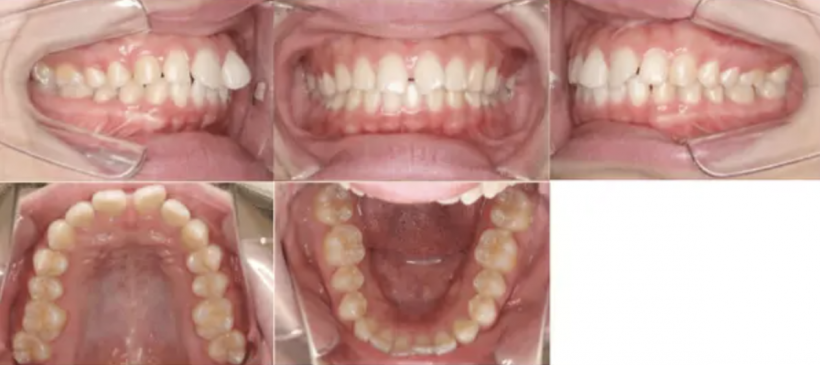

治療例①部分矯正: 28歳

【治療前】

【治療後】